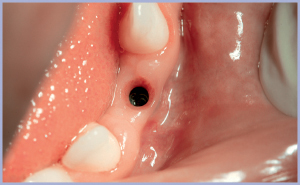

Trascorso il periodo necessario all’osteointegrazione, si rimuove il tappo di guarigione (figg. 6, 7) e si procede alla presa dell’impronta.

- Fig. 6

- Fig. 7